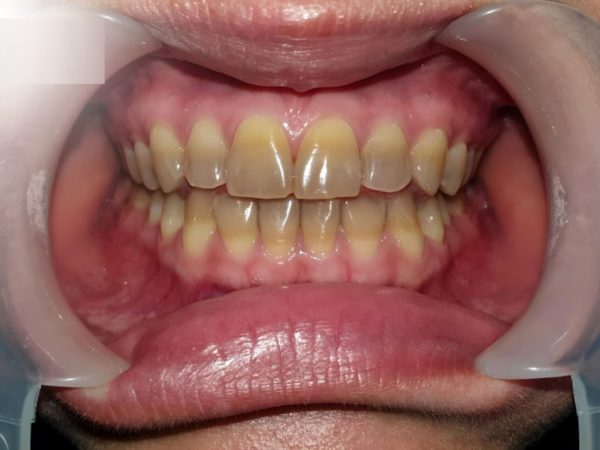

Anh Bill Huỳnh – Hành trình tìm lại nụ cười rạng rỡ cùng Platinum Dental Group

Từng mặc cảm vì hàm răng nhiễm Tetracycline cấp độ 4 – mức nặng nhất, anh Bill Huỳnh (Australia) đã tìm đến Platinum Dental Group để tìm lại nụ cười tự tin. Tình trạng răng xám vàng kéo dài nhiều năm khiến anh ngại giao tiếp, ảnh hưởng không nhỏ đến công việc và cuộc sống.

Sau khi được Dr. Lan Anh trực tiếp thăm khám, anh được chỉ định giải pháp Răng sứ thẩm mỹ toàn diện hàm trên và hàm dưới. Kết quả mang lại sự thay đổi vượt ngoài mong đợi:

- Răng trắng sáng, tự nhiên, loại bỏ hoàn toàn vết nhiễm màu nặng.

- Dáng răng – cung cười đạt tỉ lệ vàng, hài hòa với gương mặt

- Thần thái trẻ trung, gương mặt rạng rỡ và cuốn hút hơn.

Hoàn tất điều trị, anh Bill chia sẻ cảm giác như được “tái sinh”: thoải mái cười tươi, tự tin xuất hiện trong mọi khoảnh khắc. Với Platinum Dental Group, mỗi ca phục hình không chỉ là cải thiện thẩm mỹ, mà còn là hành trình đồng hành để kiến tạo một phiên bản rực rỡ hơn của chính bạn.

Hoàn tất điều trị, anh Bill chia sẻ: “Tôi chưa bao giờ nghĩ mình có thể sở hữu một hàm răng trắng sáng đến vậy. Trước đây, tôi luôn tránh cười, còn bây giờ tôi cảm thấy như được sống một cuộc đời mới tự tin, thoải mái và hạnh phúc hơn rất nhiều. Cảm ơn Platinum Dental Group và bác sĩ Lan Anh đã mang lại cho tôi nụ cười này.”